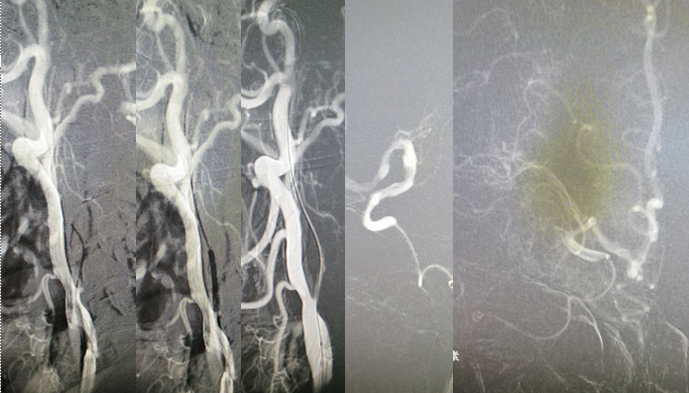

手术方案

病历夹什么径技·第151期|串联营病历夹:京广连营_https://www.jmylbn.com_新闻资讯_第75张

病历夹什么径技·第151期|串联营病历夹:京广连营_https://www.jmylbn.com_新闻资讯_第76张

病历夹什么径技·第151期|串联营病历夹:京广连营_https://www.jmylbn.com_新闻资讯_第77张

<<滑动查看下一张图片>>

• 左侧椎动脉造影见基底动脉起始处闭塞。

• 微导管造影,见基底动脉尖及左侧大脑后动脉显影不良,考虑栓塞。

• 基底动脉近端打开支架,支架形态尚可,局部发白,左侧大脑前动脉P1段栓塞。

• 支架取栓取出一小块栓子,造影见基底动脉起始处重度狭窄。

• 狭窄处予球囊扩张成形,球扩后造影见基底动脉狭窄有所改善。

• 微导管送至左侧大脑后动脉P2段,造影确认真腔后,释放支架,并支架取栓1次。

• 血栓成功取出,基底动脉侧位造影,左侧大脑后动脉再通。

• 正位造影,左侧大脑后动脉再通,无血栓逃逸,基底动脉狭窄改善,未回缩,前向血流正常,观察后结束手术。